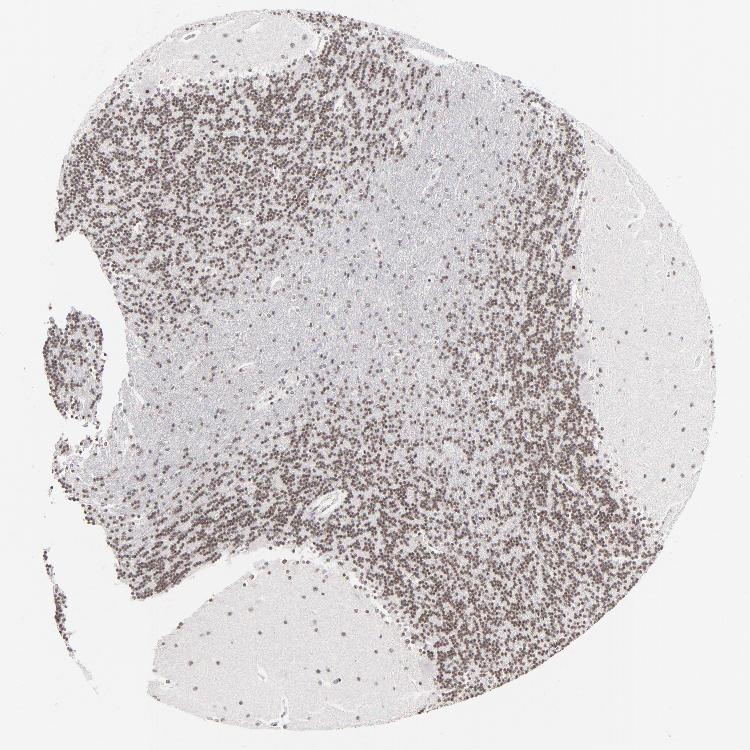

CEREBELLUM - Antibody stainingi

Antibody staining in the annotated cell types in the current human tissue is reported as not detected, low, medium, or high, based on conventional immunohistochemistry profiling in selected tissues. This score is based on the combination of the staining intensity and fraction of stained cells.

Each image is clickable and will lead to virtual microscopy that enables deeper exploration of all samples and also displays staining intensity scores, fraction scores and subcellular localization as well as patient and tissue information for each sample.

Antibody HPA003263

Purkinje cells Medium

Cells in granular layer Medium

Cells in molecular layer Low